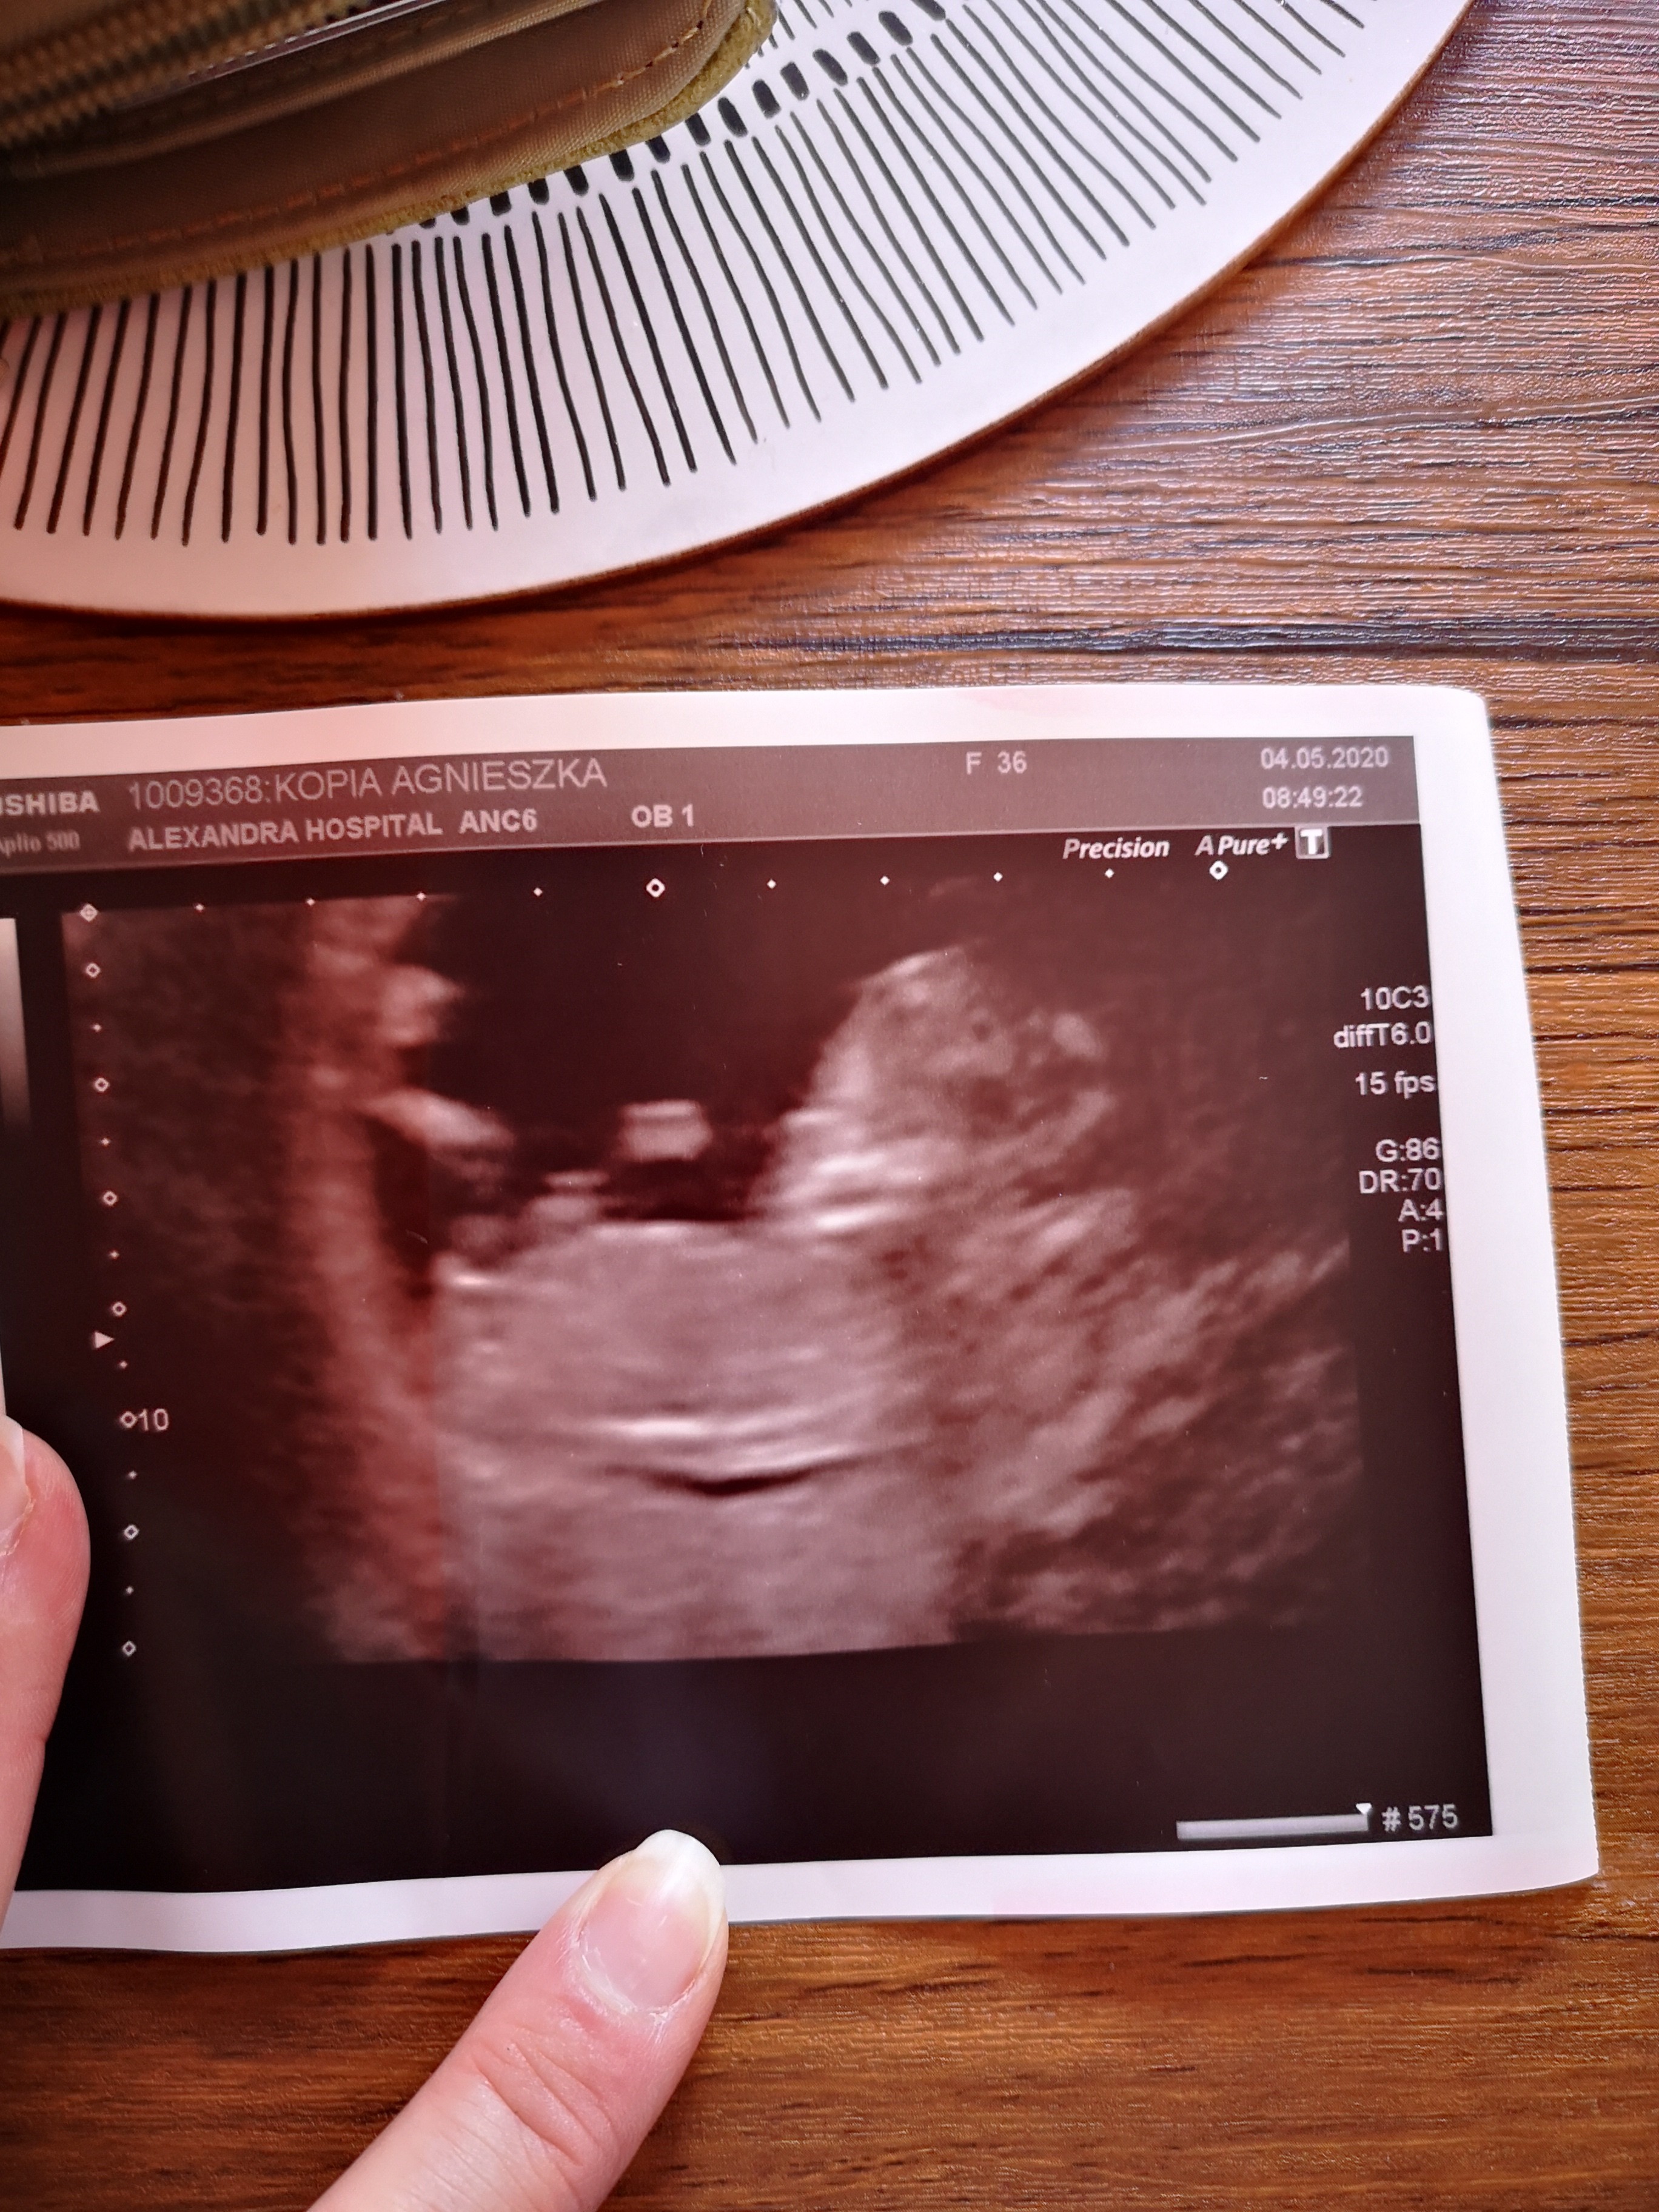

Nie wiem czy chłopak czy dziewczynka ale na ostatnim zdjęciu ślicznie trzyma rączkę za głową. [emoji3][emoji3]

Czesc dziewczyny jak myślicie to chłopiec czy dziewczynka [emoji6]